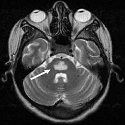

A rare cause of generalized seizures: agenesis and Lipoma of the corpus Callosum

Ahmed Belkouch, Abdelilah Mouhsine

PAMJ. 2014; 19: 384. Published 17 December 2014